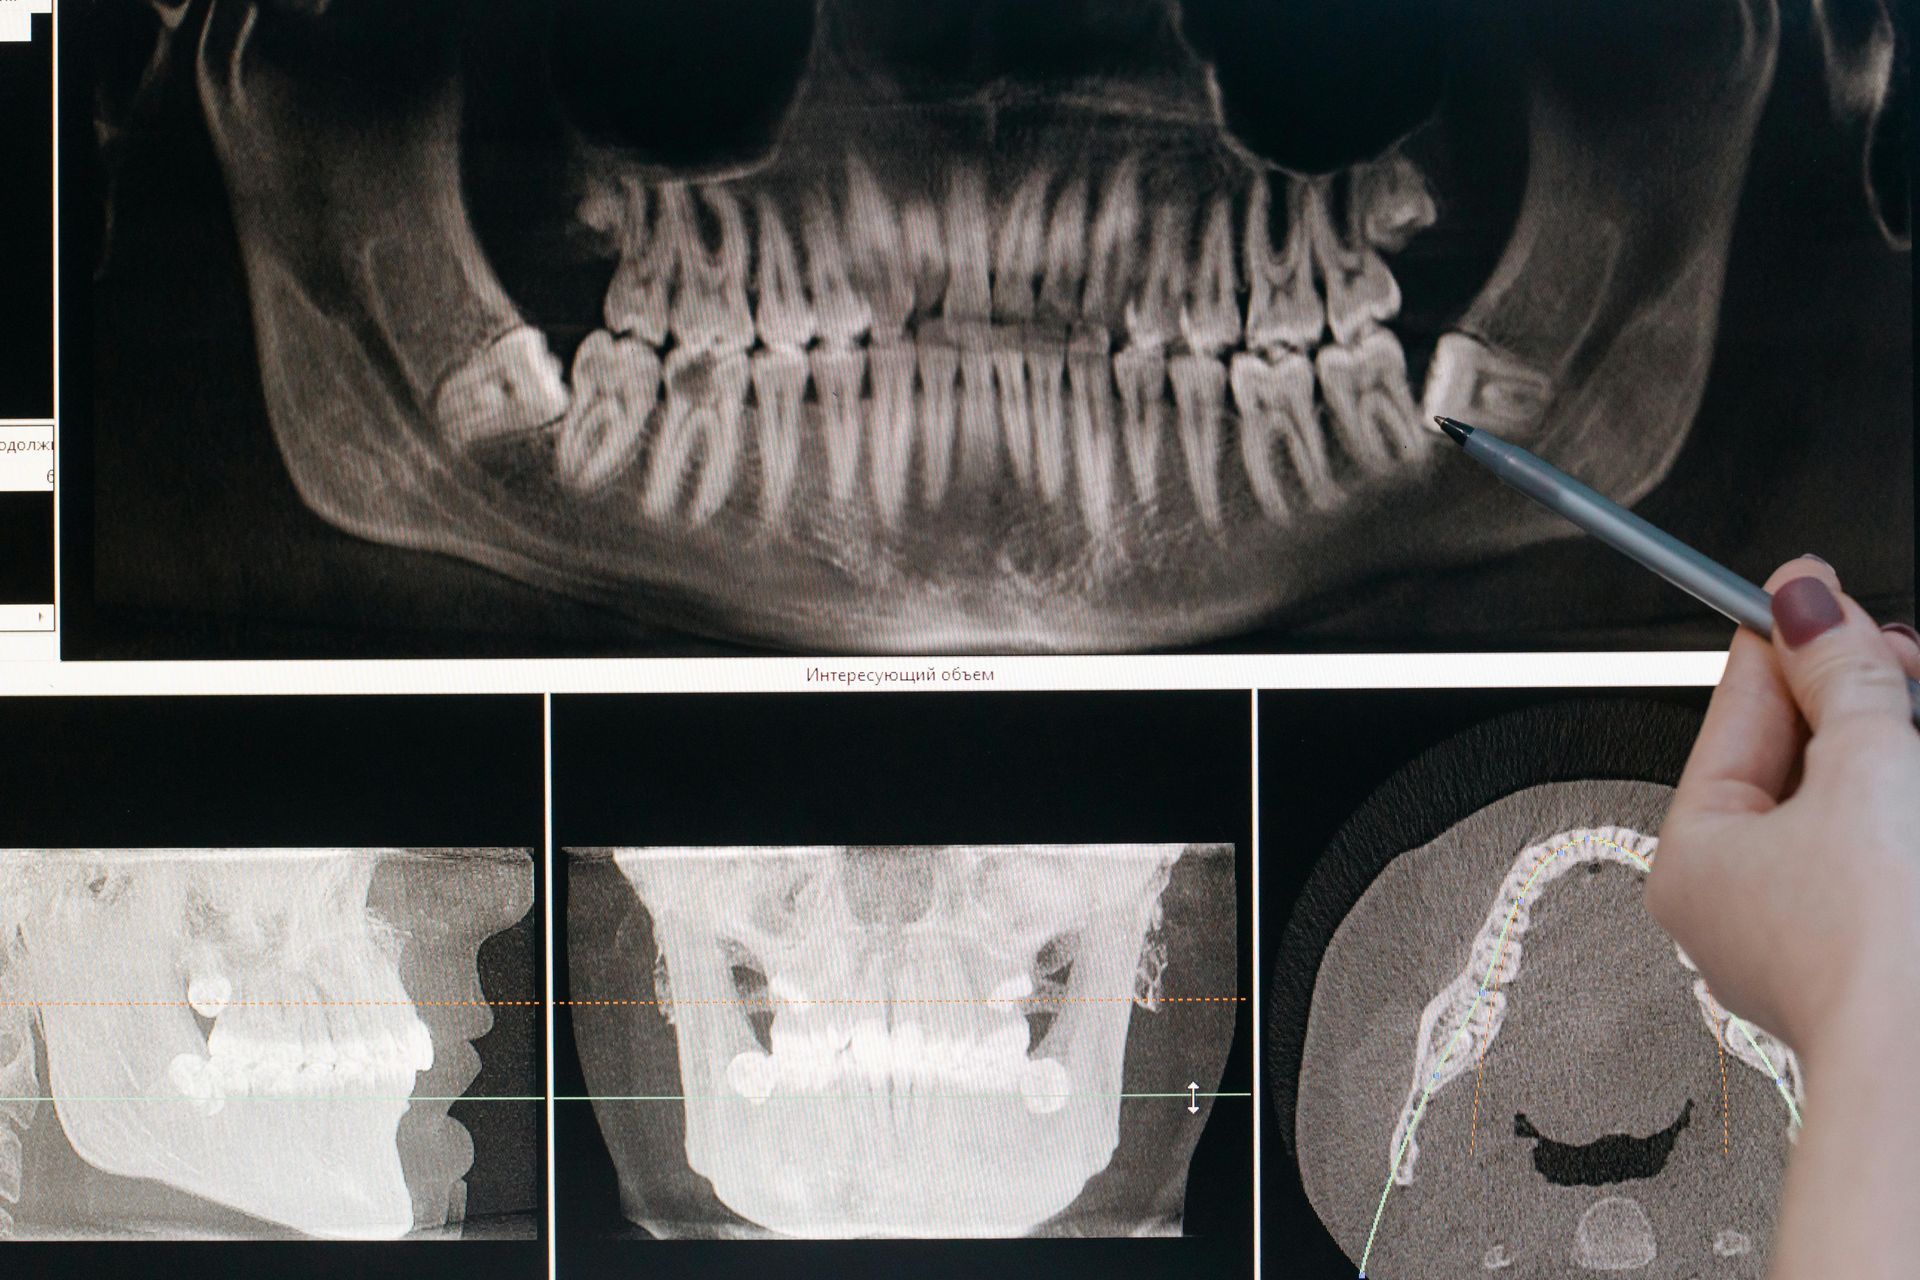

3D CBCT Imaging

At Bluegrass Periodontics, we use state-of-the-art Planmeca 3D CBCT to capture highly detailed views of your teeth, bone, and jaw.